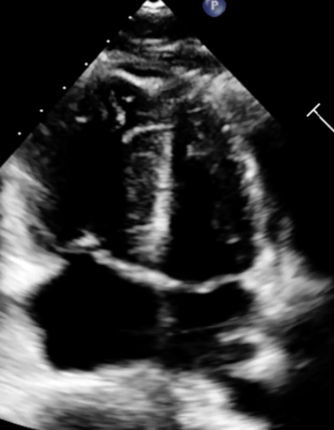

An 18-year-old female presented to the emergency department with acute-onset dyspnea, chest pain, nausea, vomiting, and syncope after four months of oral contraceptive use and active vaping. Physical examination revealed tachycardia (135 bpm) and tachypnea, with ECG showing sinus tachycardia. Laboratory studies demonstrated dramatically elevated D-dimer (12,756), elevated proBNP (660), and troponin (299 225). Echocardiography revealed the D-sign [Image 1] classic McConnell sign - severely dilated right ventricle with hyperkinetic apex and hypokinetic basal-to-mid free wall [Image 2], confirming massive PE with acute cor pulmonale. CT angiography revealed extensive bilateral pulmonary emboli with signs of right heart strain [Image 3]. Immediate anticoagulation with heparin was initiated, followed by ICU admission where alteplase was administered for massive PE. Remarkably, the patient demonstrated complete heparin resistance with no APTT response despite escalating doses over 24 hours and the decision was made to switch to rivaroxaban 15mg twice daily. Patient symptoms significantly improved on day 3 and was eventually discharged with follow up appointment to hematology.